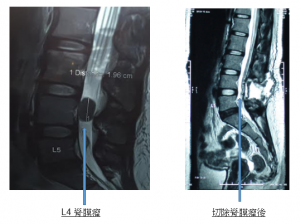

Ms. Ngai was referred to physical therapy for traction and low back stretching, but the pain in her feet increased immediately after the traction, and the pain also extended to the callosum, coccyx and the top of her foot. The foot was weak and it was very difficult to walk, the patient went to a private hospital to receive MRI imaging that night. The results of the scan showed that a large meningioma (Meningioma) had grown in the fourth segment of the lumbar spine and the cauda equina was compressed, which caused defects in the patient’s sensory and muscle nerves. In addition to meningioma, the patient also had signs of a herniated disc in the fifth lumbar spine.

Neurosurgeon performed the tumor removal surgery. The patient’s tumor compressed the cauda equina and caused nerve defects. Although the patient’s foot pain improved immediately after the operation, she still felt that the right foot was slightly weak and the right toe was also affected and numbness. After being referred by a neurosurgeon to the author for postoperative Cox® Decompression Treatment. After three weeks of treatment, the patient’s postoperative foot weakness and toe numbness were greatly improved. Since the patient also has the problem of herniated disc in the fifth lumbar spine, Cox® decompression manipulation can also be used to treat the herniated cartilage in the fifth segment.